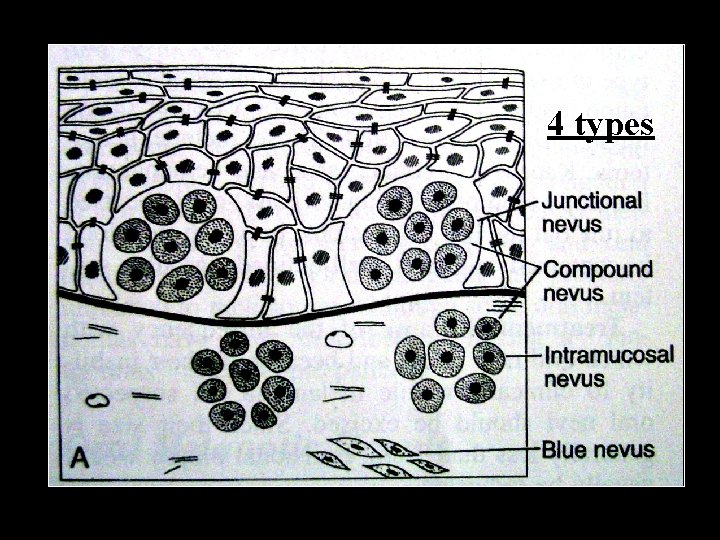

4 types